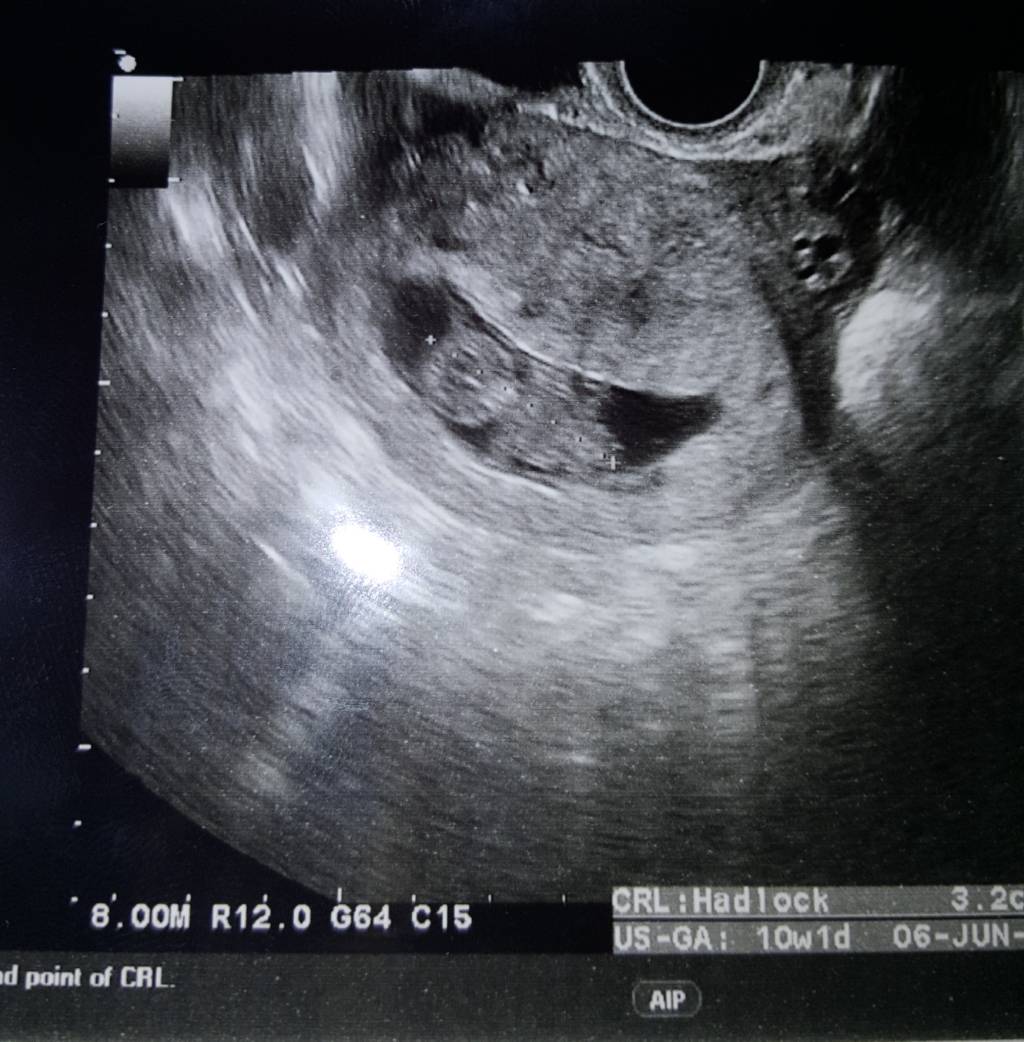

Generalnie z naszą dzidzią wszystko ok. Ma juz 3.2 cm. Według miesiączki 9+5 A według usg 10+1. Niestety lekarz zauważył jakis niewielki krwiaczek,ale mówił żebym się tego nie bała tylko wiecej uważała i odpoczywała. Stąd bylo u mnie plamienie. Co do tsh mowil ze jestem na granicy i mam powtórzyć badanie bo teraz mam największy poziom bety A wtedy ona zaniża wynik tarczycy. Więc pewnie będę musiała eutyrox brać. Mowil że toxo mam zrobic mimo że mam odporność bo w ciąży może byc reaktywacja choroby. A i jeszcze że cytomegalia bardzo ważna. I zaczepił sie mojej glukozy A ja mam wynik 82,że tez mam za dwa tygodnie powtórzyć bo to też na pograniczu.

Prenatalne i umówił mi na 27.11. Zobacz załącznik 915229